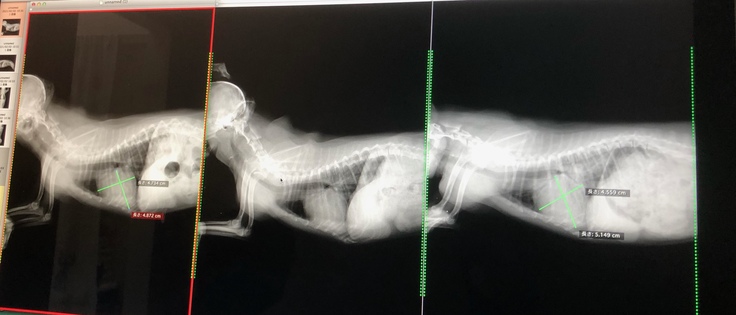

遠隔でかかりつけ医に指示を出すのですぐに病院へ行って下さい!と、おっしゃって頂き、かかりつけ医の先生からも連絡があり急いで向かいましたレントゲンで心臓や肺を確認後、【肺水腫】を起こしていました。

一番右の写真が肺水腫を起こした時のレントゲンになります

肺水腫となった原因は様々ありますが、りつの場合は、腱索が切れたことによって心臓に負荷がかかったことで起こった肺水腫とのことでした。 一度、肺水腫を起こすと余命は9ヶ月。すでに肺水腫を起こしてるため、利尿剤の注射後、酸素室に入り入院になりました。(自宅でもすぐに対応出来るように酸素室のレンタルを手配しました) 退院後は、1日酸素室で様子を見ていました。